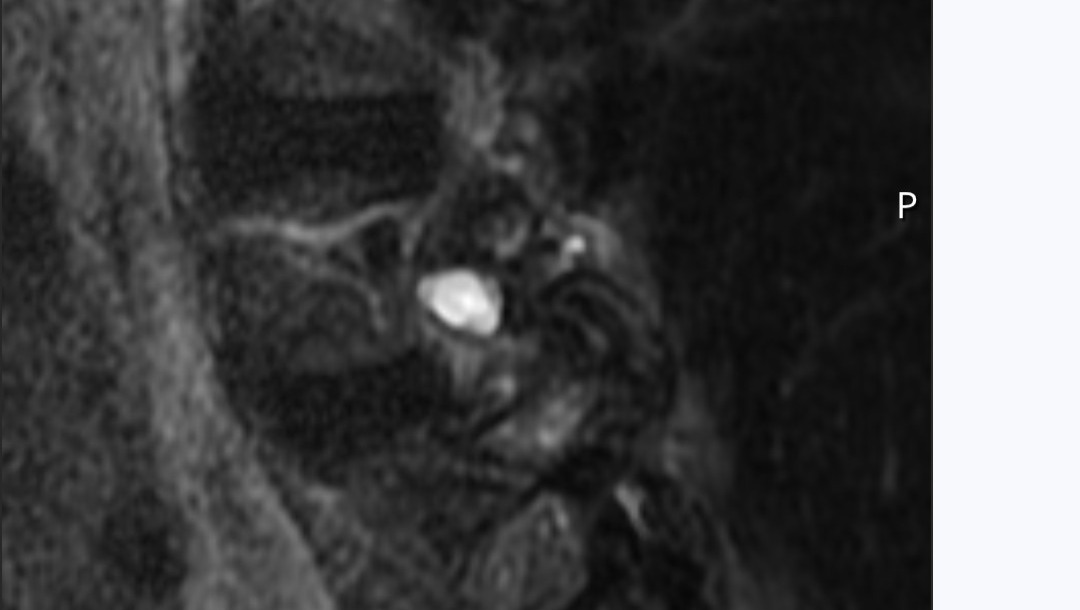

Here is the MRI of the growth from two views. As you can see it's right on the spine itself pushing on the nerves simulating a ruptured disk.

Surgery itself is relatively simple. He will cut through the back muscles and remove the growth as long as it has not grafted to the nerve root. He will remove bone to open the chamber where the root feeds the nerves to my right leg and hip.